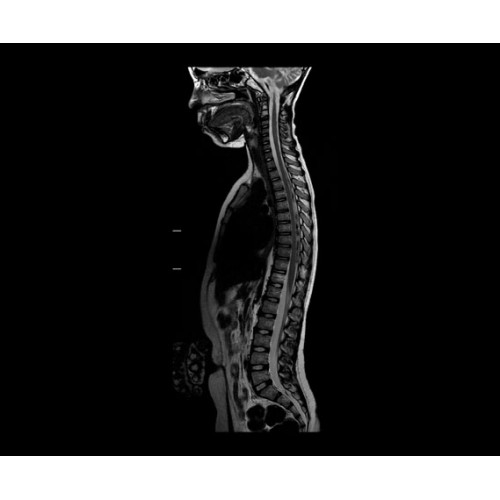

SIGNA PET/MR 3.0T — это гибридная система, в которой совмещаются две принципиально разные технологии — магнитно-резонансную томографию (МРТ) и позитронно-эмиссионную томографию (ПЭТ). Система отличающийся высокой чувствительностью и эффективностью и предназначена для диагностики в области онкологии, неврологии, кардио-васкулярных исследований, исследований воспалительных процессов.

Компания GE Healthcare представляет революционную, полностью интегрированную систему SIGNA PET/MR1, в которой сочетаются времяпролетная технология (TOF) и возможности напряженности магнитного поля 3.0 Тл. Мы поможем вам поднять исследования на более высокий уровень. SIGNA PET/MR позволяет достичь впечатляющей точности и скорости исследований, а благодаря новейшей технологии реконструкции Q.Clear2 качество изображений улучшается в два раза. Кроме того, в систему включен полный набор клинических приложений и гибких катушек для проведения любых видов исследования, открывая для вас возможности визуализации, о которых вы даже не догадывались.

• МРТ с функцией нулевого времени эхо (ZTE) отличается точностью, возможностью персональных настроек и отсутствием ионизирующего излучения. Она приходит на смену традиционному исследованию на основе рентгеновского излучения. МРТ с функцией нулевого времени эхо (ZTE) на базе SIGNA ПЭТ/МРТ является более надежной и быстрой по сравнению с системами, использующими сверхмалое время эхо (UTE).